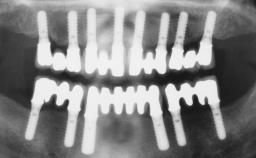

Conventional Loading of Eight Implants in the Maxilla and Final Restoration with a Full-Arch Gold-Ceramic FDP

# of Implants 8

Type of Implants One-Piece

Defining Characteristics Fully edentulous upper jaw to be rehabilitated with four or more implants

Modality Fixed hybrid bridge on 5+ implants

Defining Characteristics Fully edentulous upper jaw to be rehabilitated with an implant-borne fixed dental prosthesis